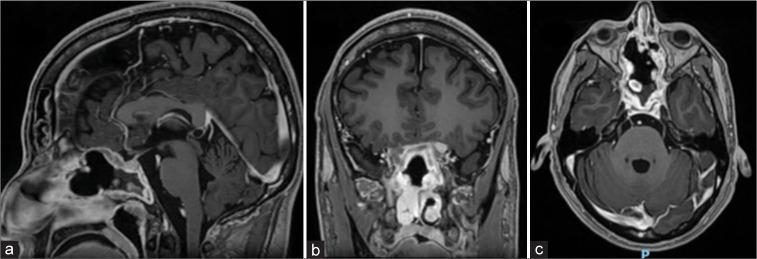

Fungal infections should always be considered in difficult-to-treat paranasal sinus conditions. Sphenoid fungal balls are characterized by the presence of dense fungal masses in the sinus cavity without invasion of surrounding tissues. This case emphasizes the importance of accurate terminology and management and also highlights the involvement of rare pathogens such as . Diagnosis is typically based on imaging studies and intraoperative findings. Accurate identification of the pathogen is crucial. Fungal infections of the paranasal sinuses, including fungus balls, can present challenges in diagnosis and treatment. , although infrequent, can cause potential life-threatening infections.

CASE DESCRIPTION

We present a 26-year-old non-HIV male patient who presented with nasal symptoms and mild headaches. The patient underwent an endoscopic exploration that revealed a soft, grayish lesion with a buttery consistency. Gross total resection was achieved and the lesion was identified as being caused by ; thus, intravenous antifungal treatment was given.

在难以治疗的鼻窦疾病中应始终考虑真菌感染。蝶窦真菌球的特征是鼻窦腔内存在致密的真菌团块,而不侵犯周围组织。本病例强调了准确的术语和管理的重要性,也突出了罕见病原体如……的参与。诊断通常基于影像学研究和术中发现。准确识别病原体至关重要。鼻窦真菌感染,包括真菌球,在诊断和治疗方面可能会带来挑战。……虽然不常见,但可导致潜在的危及生命的感染。

病例描述

我们报告一名26岁非HIV男性患者,出现鼻部症状和轻度头痛。患者接受了内镜探查,发现一个质地柔软、呈灰色、具有黄油样质地的病变。实现了全切除,病变被确定为由……引起;因此,给予了静脉抗真菌治疗。